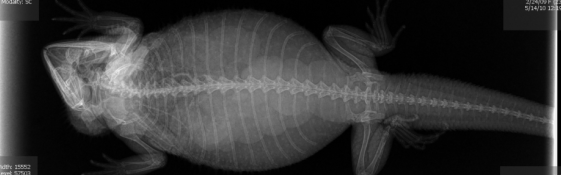

▼怀孕的猫咪